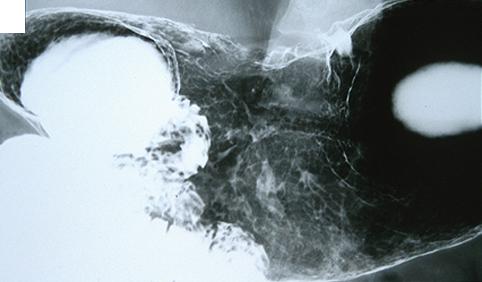

疾患(病理主体)の分類悪性上皮性腫瘍/腺癌

部位(臓器別)胃(部位)/体部

検査方法X-P

腫瘍の肉眼分類3型(潰瘍浸潤型)/

病変の最大径(ミリ)40以上

腫瘍の深達度s(a)